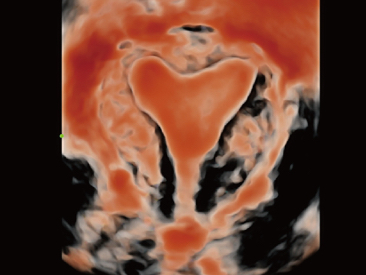

Oprócz uzyskiwania jako?ci obrazu typowego dla aparatów klasy premium, Resona 7 rozszerza mo?liwo?ci klinicznych badań USG dzi?ki rewolucyjnej funkcji V Flow, s?u??cej do oceny hemodynamiki naczyń, a tak?e najlepszej na rynku funkcji inteligentnego, automatycznego uzyskiwania p?aszczyzny na podstawie zestawów danych obj?to?ciowych 3D, umo?liwiaj?cej diagnozowanie stanu Centralnego Uk?adu Nerwowego u p?odu. Aparat Resona 7 ??czy w sobie najbardziej intuicyjn?, wielodotykow? obs?ug? za pomoc? gestów oraz wszystkie kluczowe funkcje kliniczne, co sprawia i? jest prawdziwym liderem we wprowadzaniu innowacji w ultrasonografii.